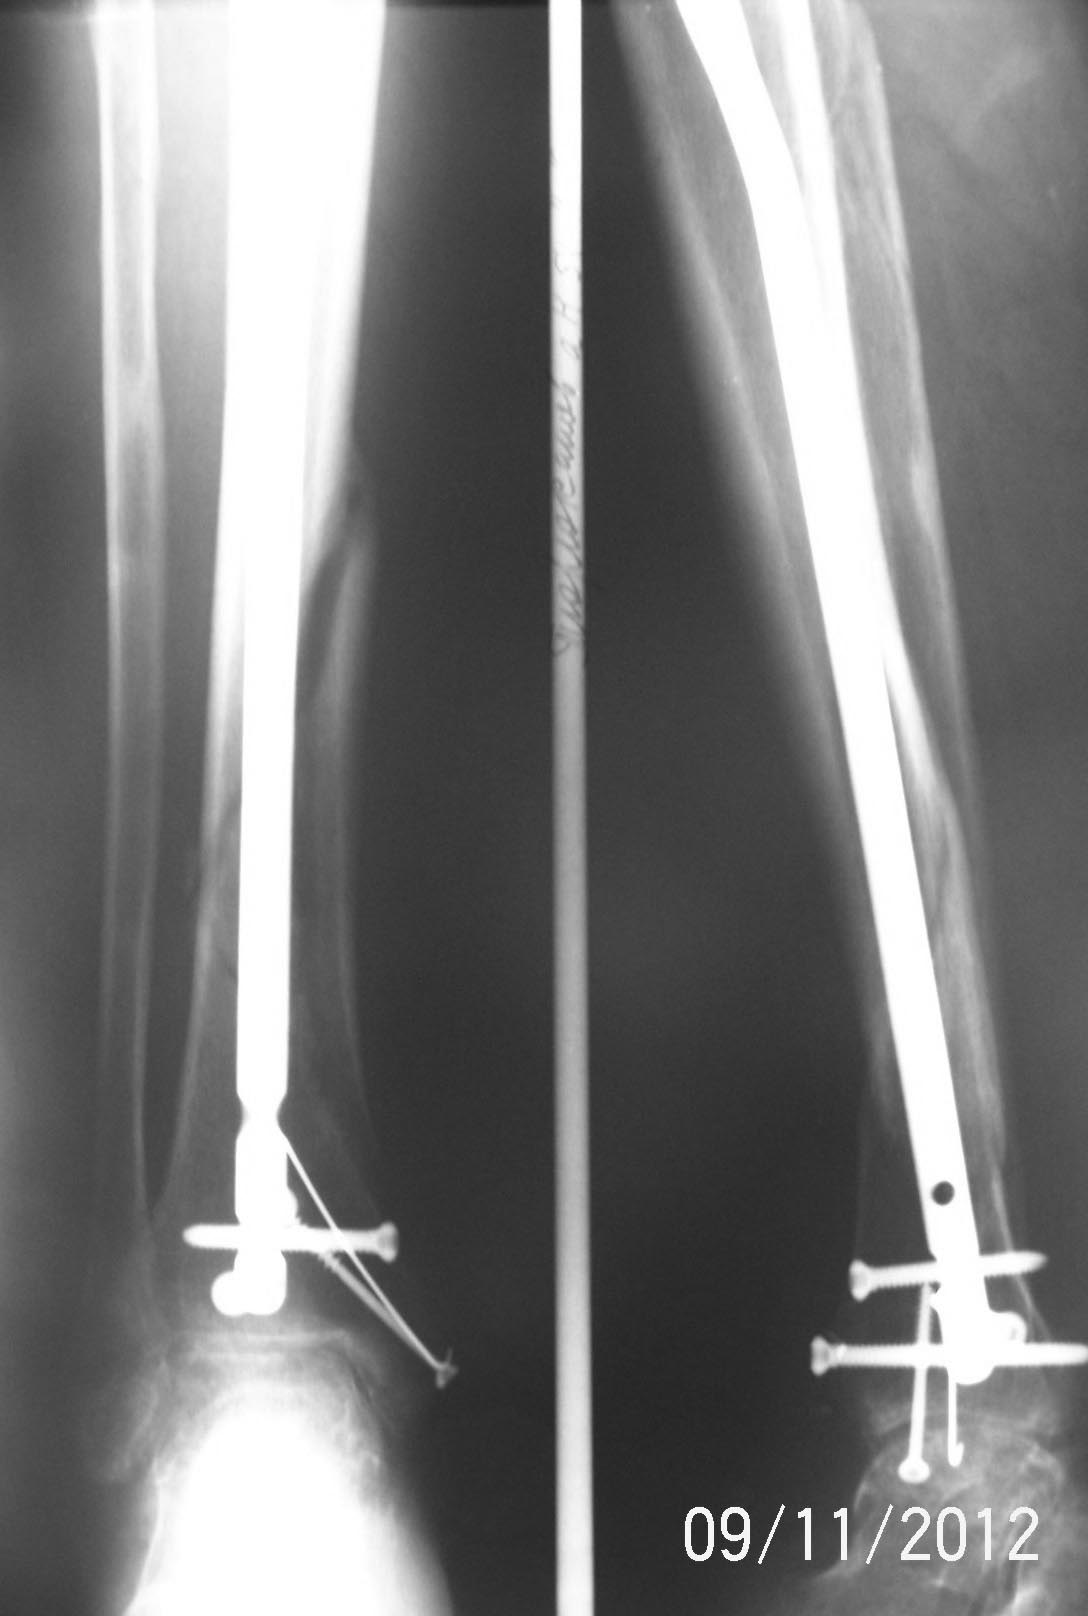

[Ortho] Нет сращения через полгода после штифтования голени

Имя     : 100_3343.JPG